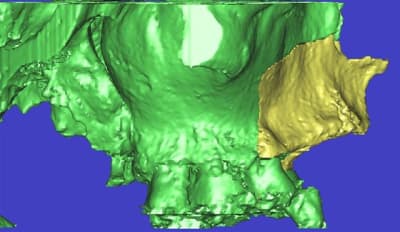

dar_3d3_if27ok.jpg

l'étude en partant des blocs standards

La première diapo est un essai pour justifier le concept (os non destiné à une utilisation greffe)

la deuxième est "tapée" dans une tête de femur de mauvais qualité (rejetée)

la troisième et suivante ce sont "les greffons" définitifs.

concept très prometteur. on obtient effectivement un contact intime du greffon avec le site receveur.